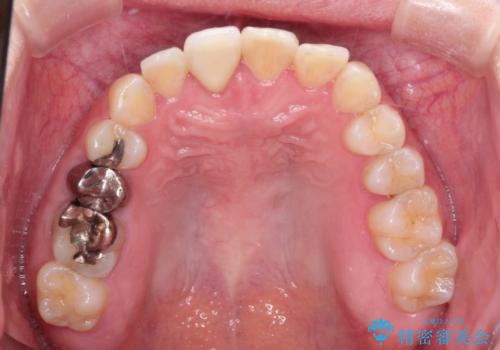

インビザラインにて矯正治療後の前歯のセラミッククラウン治療

インビザラインによる矯正治療で前歯の歯並びを改善し、セラミッククラウン装着により歯の形態の回復をする計画としました。

矯正とセラミックを併用することで、より完成度の高い状態に仕上げることができました。